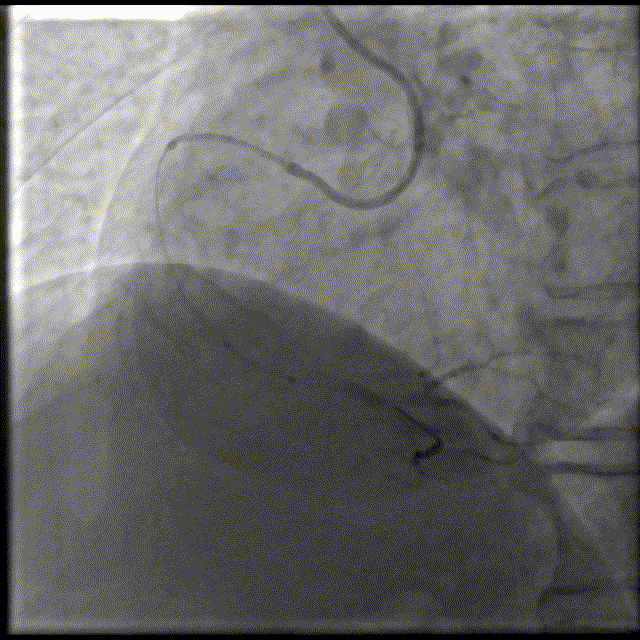

冠脉造影

回旋支:近段钙化,全程管壁不光滑,远段狭窄50%-60%。

左主干:钙化;

前降支:全程管壁不光滑,开口及近中段钙化,发出D1后狭窄40-50%。可见S-RCA远段形成1级侧支。

右冠脉:近中段钙化,中段狭窄40-50%,远段100%闭塞。

右冠近中段可见钙化

头位造影:RCA近中段钙化迂曲,第二转折处中度狭窄。